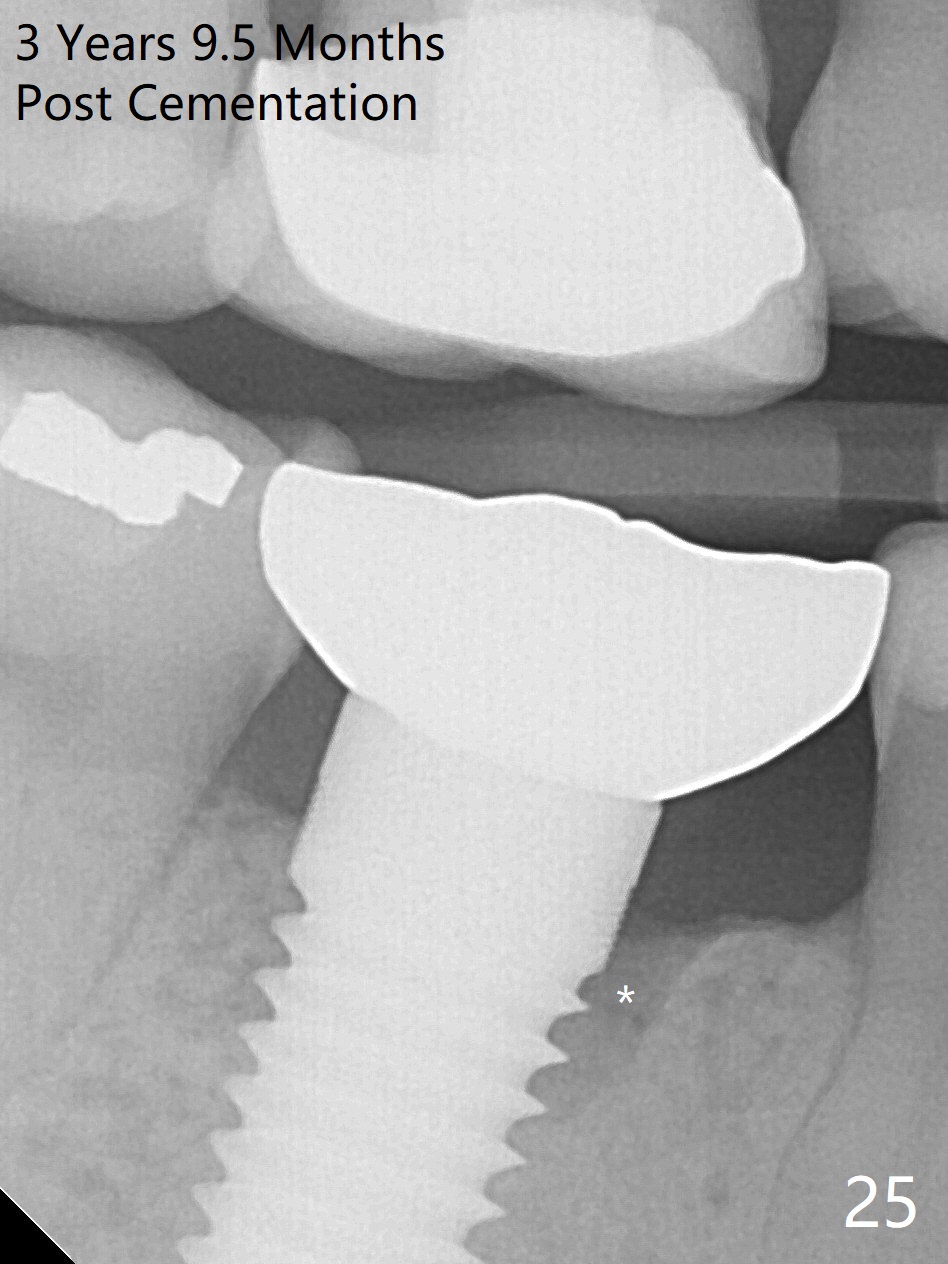

The patient will return for immediate implant at #14. Do not forget placing an implant as palatal as possible. There is no sign of infection at #30 three years 9.5 months post cementation because of water pik for #3 endo failure (Fig.25,26).